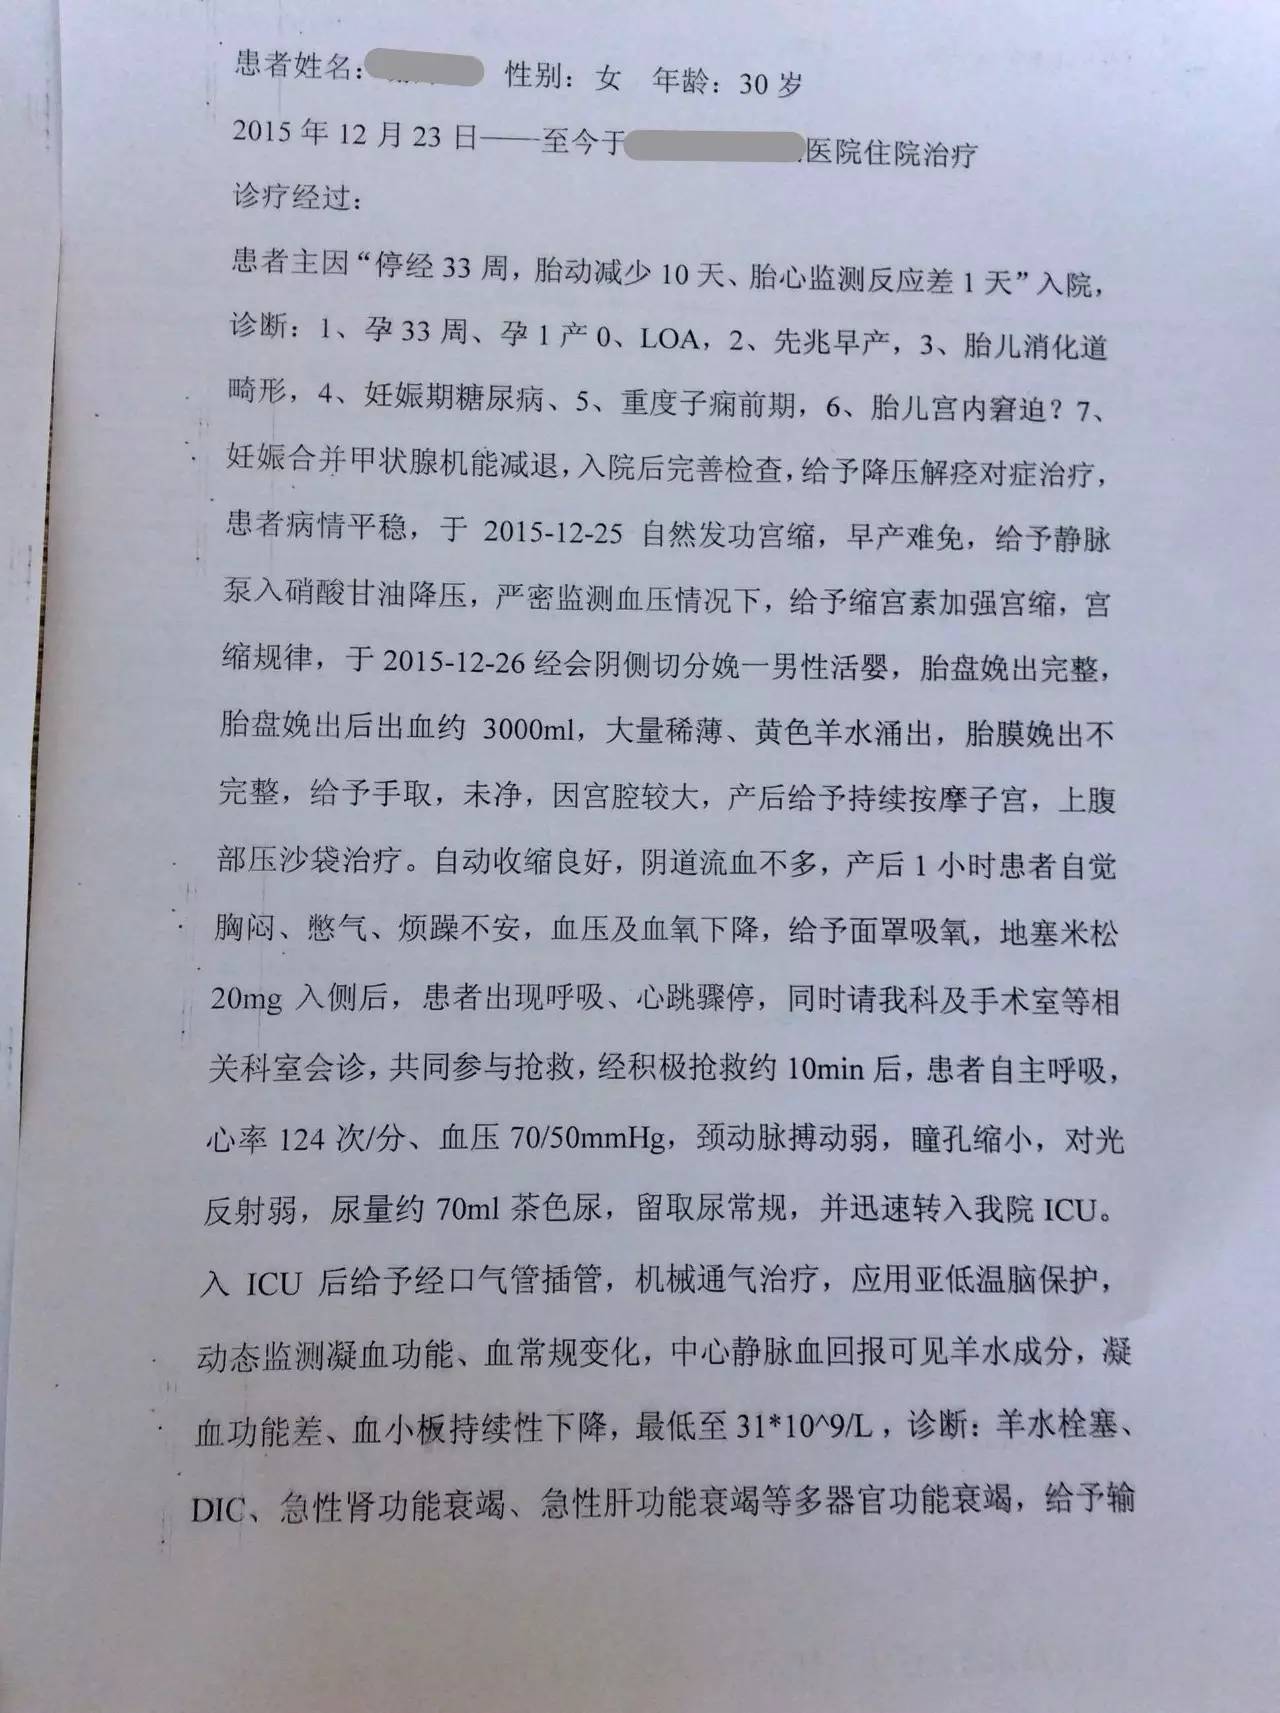

▼患者病程记录资料

▼患者检查报告资料

▼患者影像资料